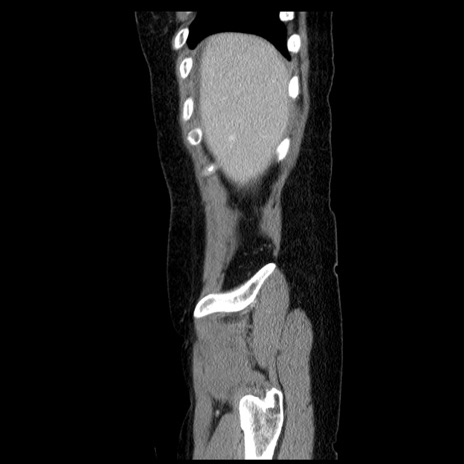

症例6(矢状断像)

冠状断像

【症例】50歳代女性

【既往歴】卵巣癌術後(8年前に当院で卵巣摘出)

【身体所見】 意識清明、腹部:平坦、腸蠕動音→、やや硬、下腹部自発痛・圧痛あり、反跳痛あり、筋性防御なし。

【データ】WBC 16000、CRP 0.01